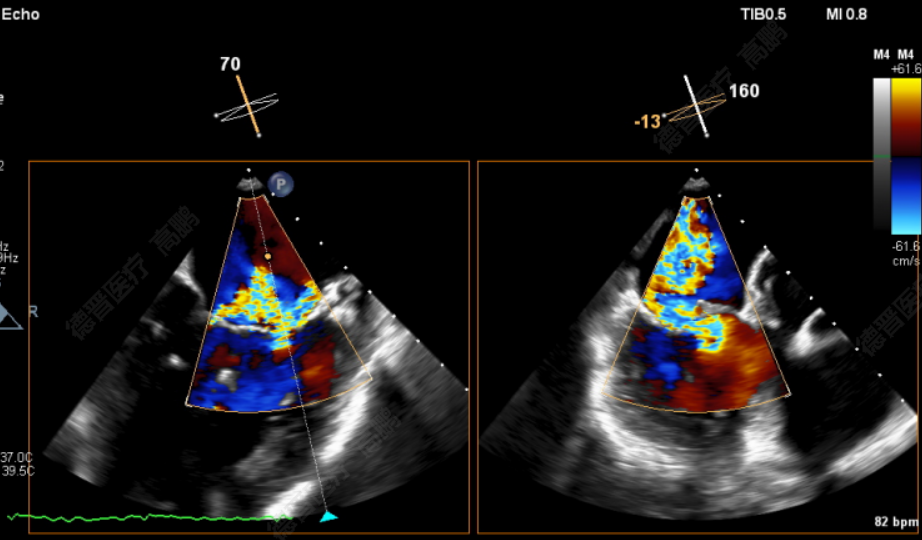

患者为75岁老年男性。反复气促、胸闷2年余,加重1月就诊福建省立医院。经胸心脏彩超提示:二尖瓣后叶重度脱垂伴返流4+、后叶腱索断裂;经食道超声心动图提示:二尖瓣后叶P2区重度脱垂伴返流4+。既往有高血压病、冠心病病史。

患者为72岁老年男性,反复胸闷、气促1年,加重1周就诊福建省立医院。心脏彩超提示:二尖瓣前叶脱垂伴返流4+;食道超声心动图提示:为二尖瓣后叶A1区偏前联合交界处重度脱垂伴返流4+。既往有COPD(肺功能提示重度阻塞性通气功能障碍)、高血压病病史。